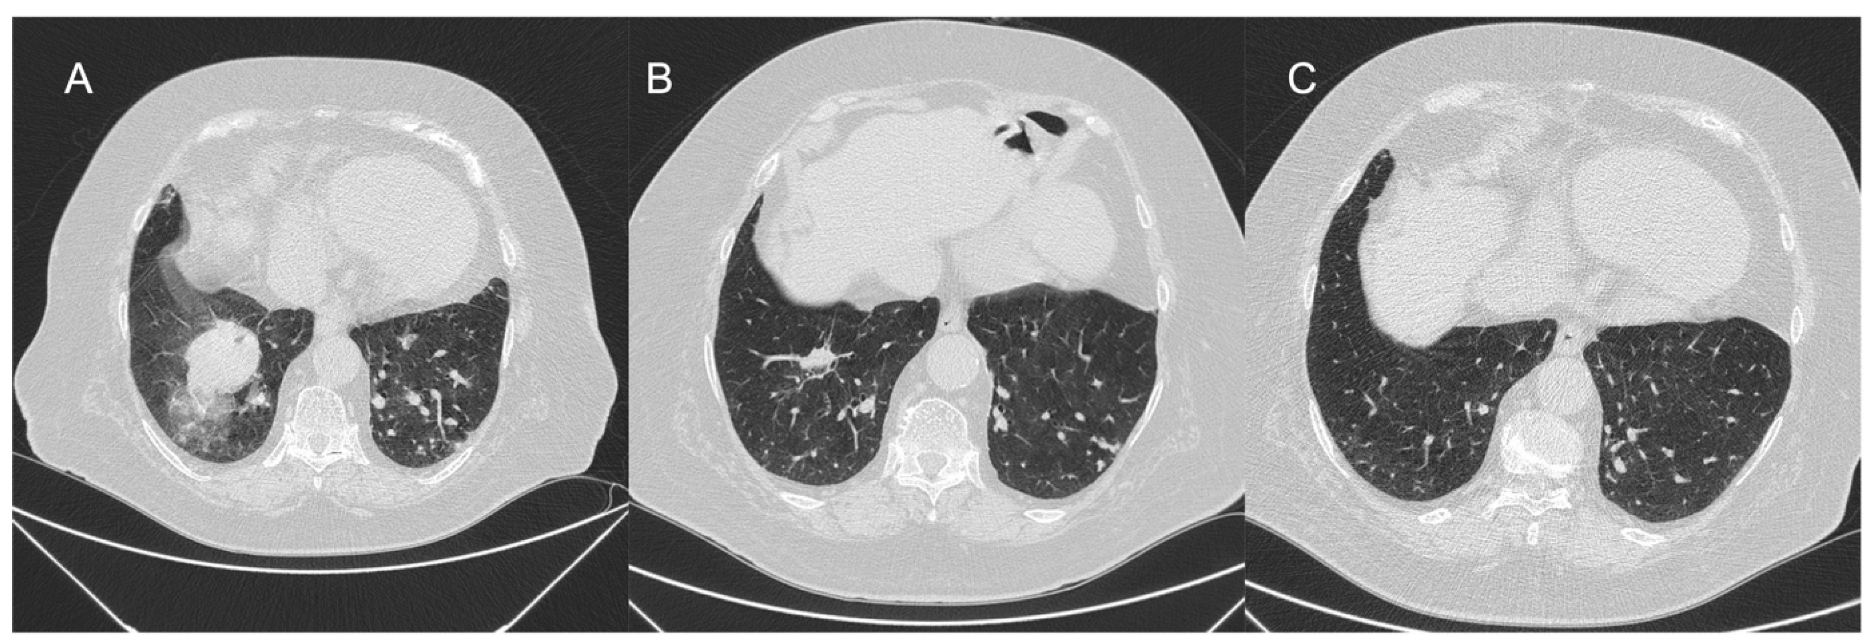

- Ejiri, K.; Ogawa, A.; Fujii, S.; Ito, H.; Matsubara, H. Vascular Injury Is a Major Cause of Lung Injury After Balloon Pulmonary Angioplasty in Patients With Chronic Thromboembolic Pulmonary Hypertension. Circ. Cardiovasc. Interv. 2018, 11, e005884. [Google Scholar] [CrossRef] [PubMed]

- Inami, T.; Kataoka, M.; Shimura, N.; Ishiguro, H.; Yanagisawa, R.; Taguchi, H.; Fukuda, K.; Yoshino, H.; Satoh, T. Pulmonary edema predictive scoring index (PEPSI), a new index to predict risk of reperfusion pulmonary edema and improvement of hemodynamics in percutaneous transluminal pulmonary angioplasty. JACC Cardiovasc. Interv. 2013, 6, 725–736. [Google Scholar] [CrossRef] [PubMed]